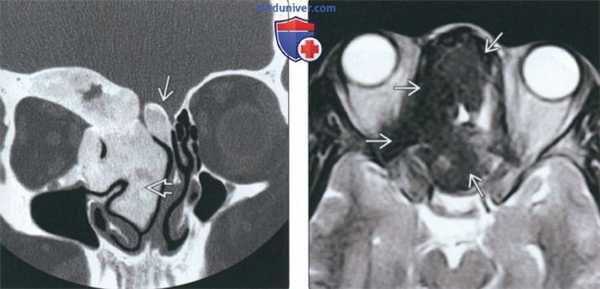

При воспалительных изменениях в ретроантральной жировой клетчатке верхнечелюстной пазухи на РКТ повышаются денситометрические значения ее плотности [10]. При одностороннем процессе отмечается выраженная асимметричность значений плотностей (рис. 4).

Рис. 4. Рентгеновская компьютерная томограмма околоносовых пазух. Аксиальная проекция, костное окно.

В 63,2% случаев на РКТ при выявлении одонтогенного верхнечелюстного синусита отмечалось уплотнение жировой клетчатки. Исследователи связывают это с переходом воспалительной инфильтрации пристеночной слизистой по периваскулярным пространствам к ретромаксиллярной клетчатке [7, 11, 12].